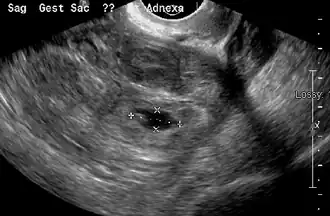

Transvaginal ultrasonography

An ultrasound showing a gestational sac with the fetal heart in the fallopian tube has a very high specificity for ectopic pregnancy. It involves a long, thin transducer, covered with the conducting gel and a plastic/latex sheath and inserted into the vagina.[38] Transvaginal ultrasonography has a sensitivity of at least 90% for ectopic pregnancy.[5] The diagnostic ultrasonographic finding in ectopic pregnancy is an adnexal mass that moves separately from the ovary. In around 60% of cases, it is an inhomogeneous or a noncystic adnexal mass, sometimes known as the "blob sign". It is generally spherical, but a more tubular appearance may be seen in the case of hematosalpinx. This sign has been estimated to have a sensitivity of 84% and a specificity of 99% in diagnosing ectopic pregnancy.[5] In the study estimating these values, the blob sign had a positive predictive value of 96% and a negative predictive value of 95%.[5] The visualization of an empty extrauterine gestational sac is sometimes known as the "bagel sign", and is present in around 20% of cases.[5] In another 20% of cases, there is visualization of a gestational sac containing a yolk sac or an embryo.[5] Ectopic pregnancies where there is visualization of cardiac activity are sometimes termed "viable ectopic".[5]

-

Transvaginal ultrasonography of an ectopic pregnancy, showing the field of view in the following image -

A "blob sign", which consists of the ectopic pregnancy. The ovary is distinguished from it by having follicles, whereof one is visible in the field. This patient had an intrauterine device (IUD) with progestogen, whose cross-section is visible in the field, leaving an ultrasound shadow distally to it. - Ultrasound image showing an ectopic pregnancy where a gestational sac and fetus have been formed